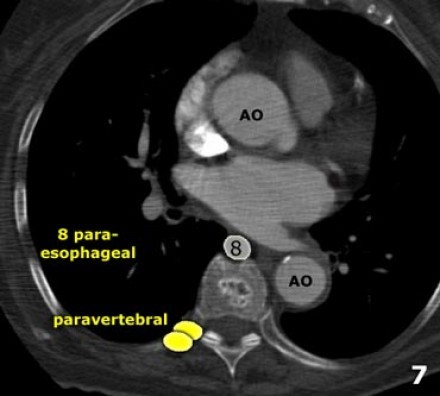

8. Linfonodos Paraesofageanos

Estes linfonodos estão abaixo dos linfonodos carinais e se estendem caudalmente até o diafragma.